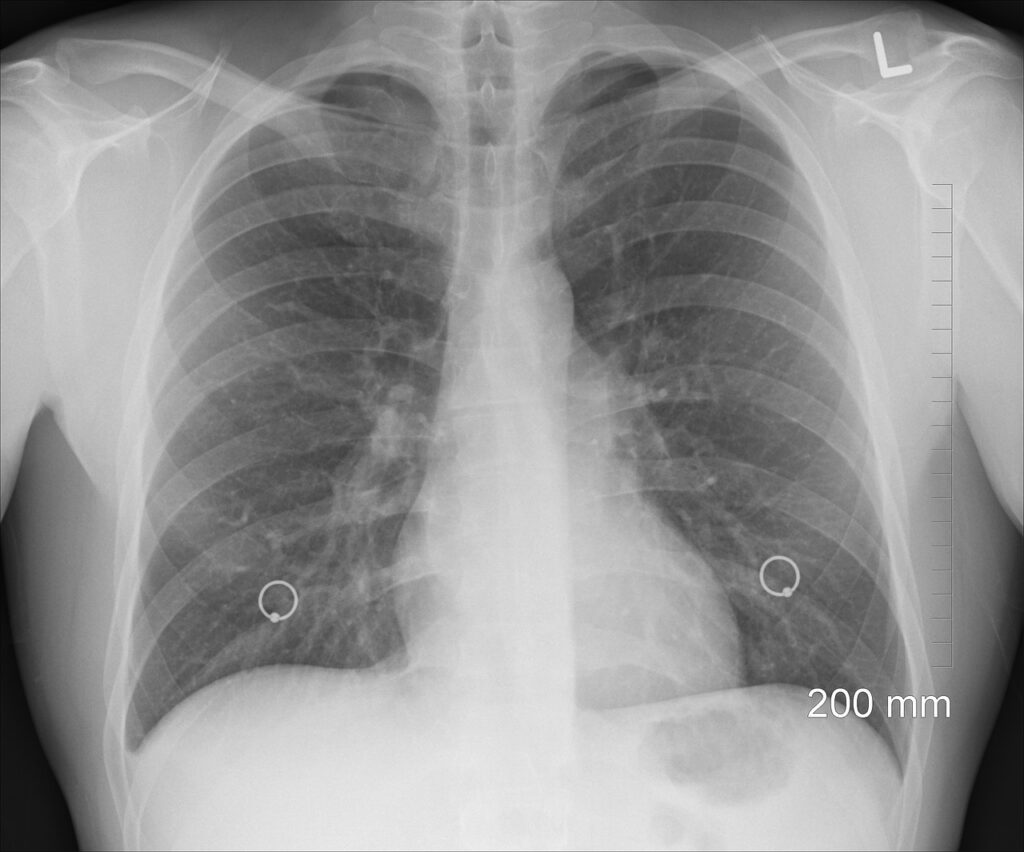

En cuanto al diagnóstico precoz, el experto remarca que estudios como el Early Lung Cancer Action Project (ELCAP) demostraron hace años el beneficio del cribado de cáncer de pulmón. Según informa el Dr. Pío Osés, la Comisión Europea ha recomendado la introducción del cribado para las personas fumadoras o exfumadoras que cumplen criterios relacionados con el hábito tabáquico (el 90% de estos tumores aparecen en fumadores) y la edad. “Sin embargo, la implantación del cribado del cáncer de pulmón en Europa se enfrenta a varios retos, como la limitación de recursos y la diversidad de los sistemas sanitarios, que contribuyen a una dispar disponibilidad de sistemas de detección”, apunta.

En esta línea, han trabajado en el desarrollo de un algoritmo mediante el uso de biomarcadores tumorales, con el fin de ofrecer una prueba diagnóstica económica, estandarizada, poco invasiva y accesible a cualquier laboratorio de cualquier hospital. El uso de este algoritmo ofrecería unos resultados de sensibilidad, especificidad y valores predictivos muy superiores a los obtenidos por otras pruebas. “Hemos evaluado los resultados de la aplicación de este panel de biomarcadores en diferentes hospitales y hemos realizado una validación externa de los resultados de la aplicación de este algoritmo con unos resultados muy positivos, mejores que los obtenidos por otras pruebas como las técnicas de imagen, entre otras”, subraya el Dr. Barco.

De esta forma, como asevera el Dr. Barco, el laboratorio podría participar aplicando este algoritmo de biomarcadores a los pacientes de riesgo (aquellos con historia clínica compatible con un posible cáncer de pulmón), “agilizando el posible diagnóstico y, ante un posible cribado, preseleccionando aquellos con un riesgo alto de cáncer, a los que se les realizarían las pruebas de imagen. Por lo tanto, se podría llegar a un número mayor de pacientes optimizando los recursos y ayudando a un cribado más eficiente”.